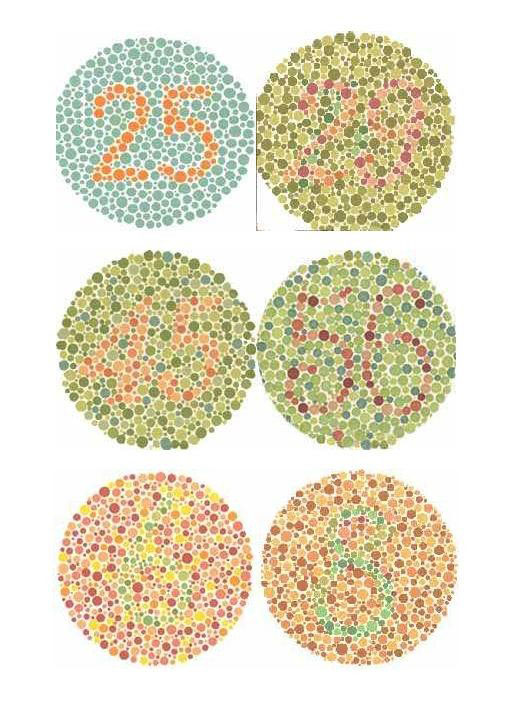

از هر صد نفر ، هشت نفر از بیماری کوررنگی رنج میبرند. حال شما فکر کنید دندانپزشکی که کور رنگی دارد چقدر دچار اشتباه در حین انتخاب رنگ خواهد بود .شکل هایی را که در زیر مشاهده می کنید تست کوررنگی هستند که اگر شما قادر به تشخیص اعداد باشید مبتلا به کوررنگی نخواهید بود .

آزمایش ای شی هارا ( فرد کوررنگ قادر به تشخیص اعداد نخواهند بود . )